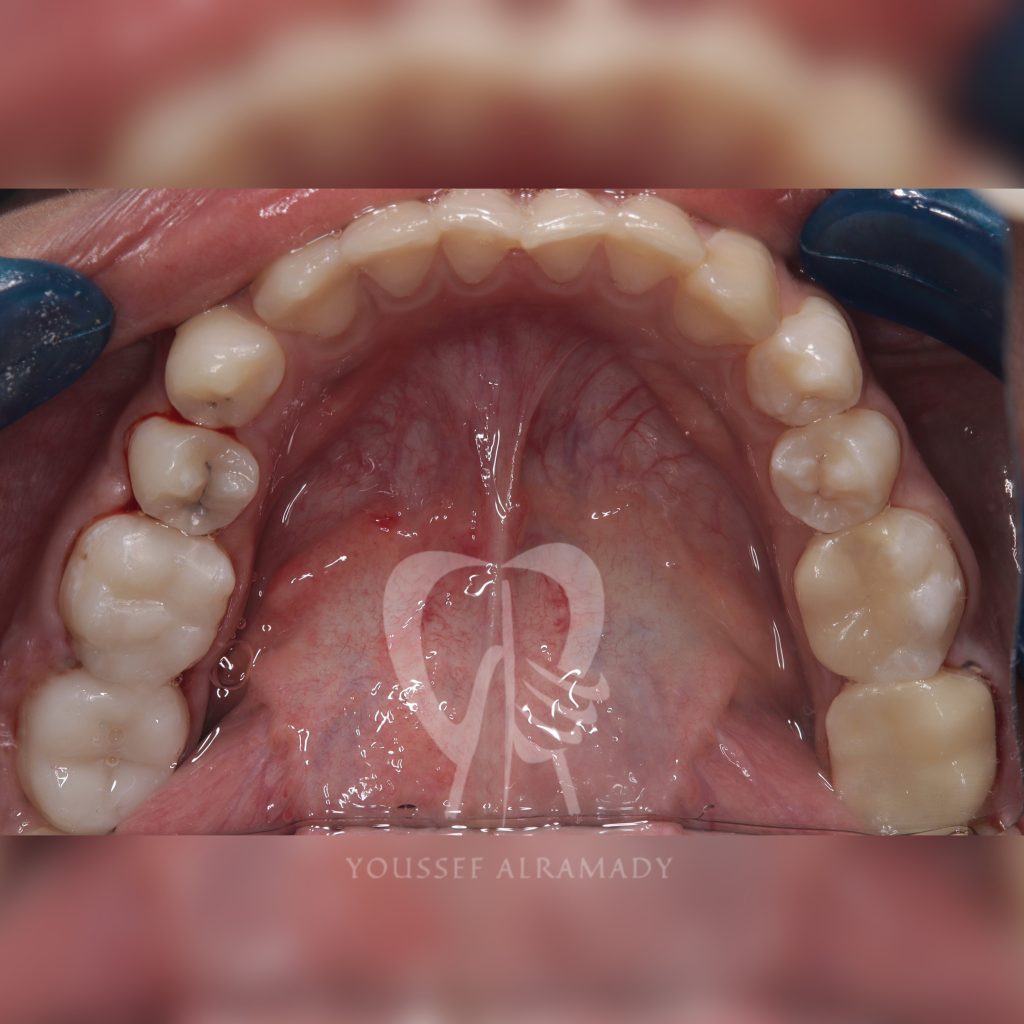

Case study to assess durability and longevity of 2 different types of indirect restorations in the same patient

Restoring teeth no.36 & 37 with indirect composite restoration (nanohybrid)

Restoring teeth no.46 & 47 with emax (lithium disilicate )